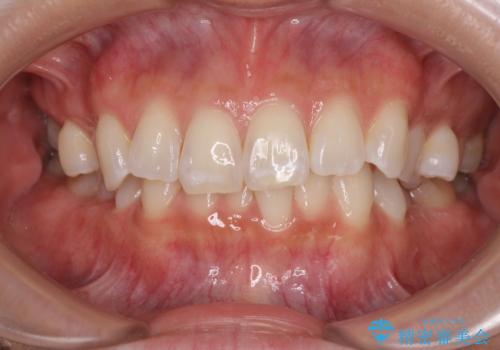

受け口と八重歯を改善 インビザライン矯正治療